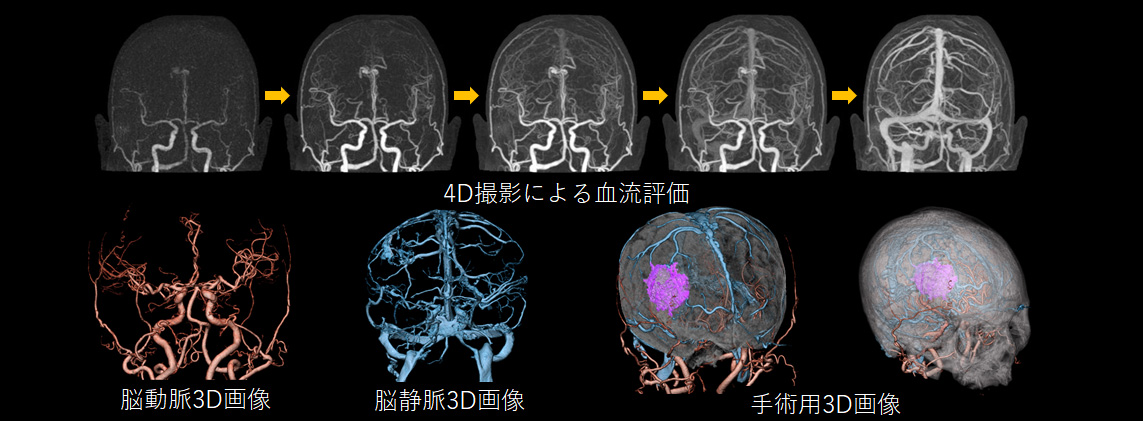

頭部領域 では320列面検出器を活かした高精細画像が撮影可能

頭部領域では出血や梗塞、腫瘍などさまざまな病気が存在します。その原因となる血管の形や太さは人によって様々ですが、当院のCTと造影剤という薬剤を用いることでそれらを正確に画像化することができます。特に4D撮影という特殊な撮影を行うことで、血液の流れを見ることが可能となり血流の違いによる病気の発見にも役立ちます。